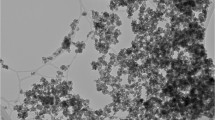

Scanning electron microscopy (SEM) studies were carried out using a Focused Ion Beam Zeiss Neon40 microscope operating at 5 kV, equipped with an energy dispersive X-ray (EDX) spectroscopy system. Samples were deposited on a silicon disc mounted with silver paint on pin stubs of aluminum, and sputter-coated with a thin layer of carbon to prevent sample charging problems.

Characterization of ACP

The morphology of ACP, which is displayed in Fig. 1a and b, reflect the influence of hydrothermal and aging conditions. ACP particles obtained using open aging, exhibit an pseudo-spherical morphology of nanometric dimensions. The average dimensions of ACP pseudo-spheres are displayed in Table 2.